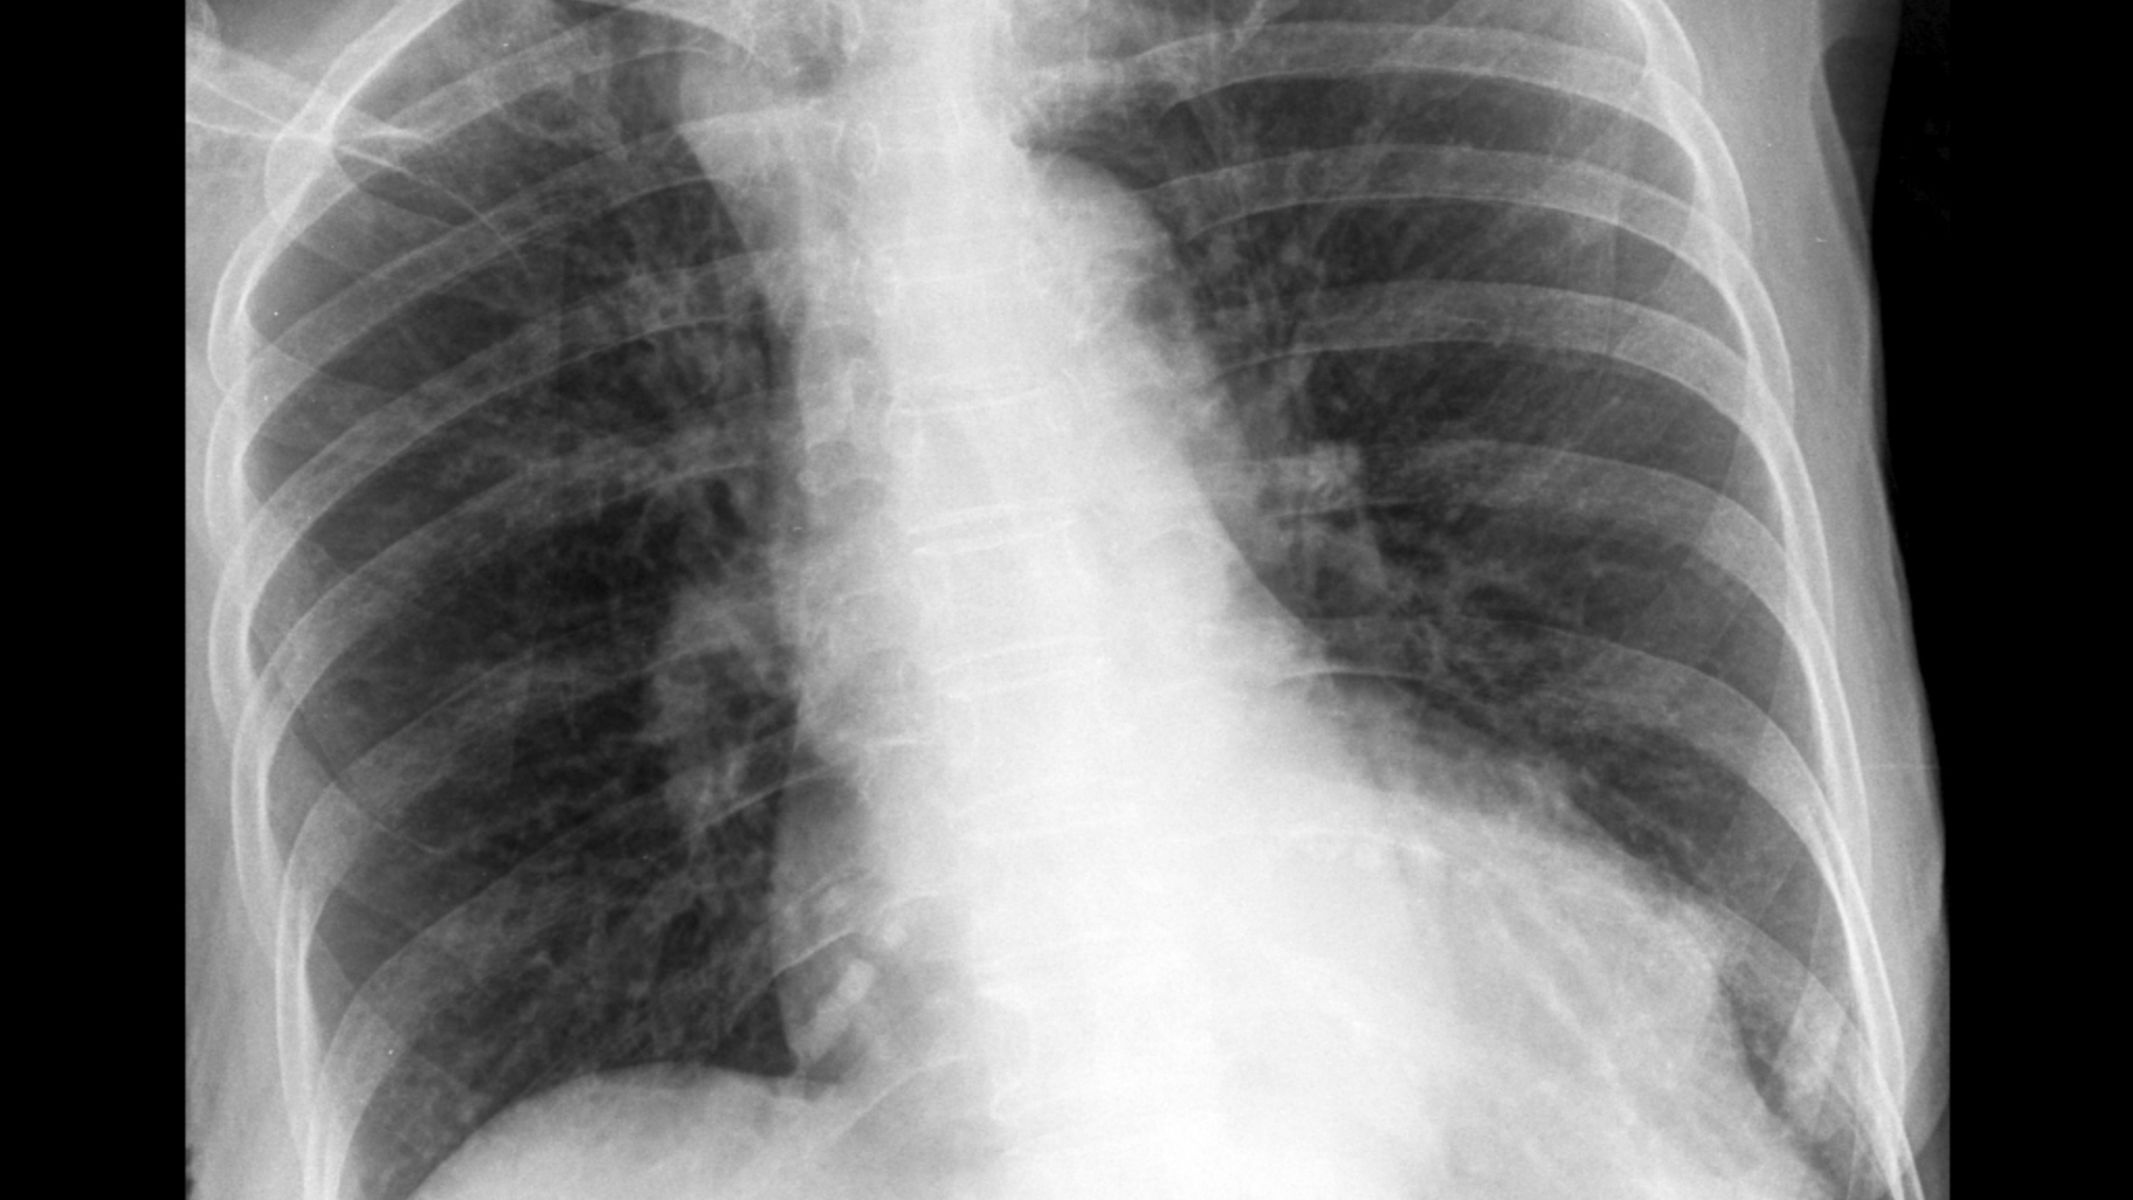

Chụp MRI phổi là kỹ thuật chẩn đoán hình ảnh sử dụng từ trường mạnh kết hợp với sóng radio để tạo ra hình ảnh chi tiết của phổi và các cấu trúc xung quanh. Phương pháp này không sử dụng tia X nên không gây phơi nhiễm bức xạ ion hóa cho cơ thể.

Khác với chụp X-quang hay CT vốn dựa nhiều vào sự khác biệt về tỷ trọng mô, MRI hoạt động dựa trên tín hiệu từ các phân tử hydro trong cơ thể. Nhờ đó, MRI có khả năng phân biệt mô mềm tốt hơn trong một số tình huống nhất định.

Một trong những giá trị nổi bật của chụp MRI phổi là khả năng đánh giá các tổn thương phức tạp liên quan đến mô mềm. MRI có thể hỗ trợ phát hiện khối u phổi, tổn thương viêm lan tỏa hoặc bất thường cấu trúc mà các phương pháp khác chưa làm rõ.

Trong một số trường hợp, hình ảnh MRI giúp bác sĩ phân biệt tổn thương lành tính và ác tính dựa trên đặc điểm tín hiệu, từ đó hỗ trợ định hướng chẩn đoán và kế hoạch điều trị.